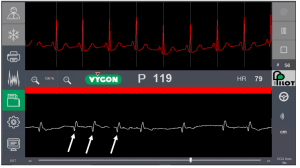

También se basa en la interpretación de la onda P: el trazado intracavitario (abajo) enseña cómo va creciendo la onda P cuanto más se acerca el catéter al corazón y el trazado superior sirve de referencia.

Mientras el catéter va avanzado de forma correcta hacia y en la VCS, la barra central de color es verde. En cuanto, la onda P se vuelve bifásica, la barra de color indica con el color naranja que el catéter está demasiado lejos.

El sistema Pilot, tiene una característica adicional para ver la evolución de la onda P: calcula la altura de la onda P en el trazado intracavitario y le da entonces un valor numérico (en el centro de la pantalla) que va creciendo o disminuyendo siguiendo la evolución de la onda P en el ECG.